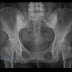

View Inverted Napoleon Hat Sign Background. Inverted magnified image of l5 showing the hat like contour of l5 vertebra. Radiograph of ls spine shows abnormal contour of the l5 vertebra.

The license could not be verified: Spondylolisthesis napoleon hat sign inverted kick beater inverted cervical x ray. Chilaiditi sign (& syndrome) σύνδρομο κηλαϊδίτη * ( chilaiditi syndrome / colonic interposition 6 ): Inverted napoleon hat sign definition in the dictionary english.